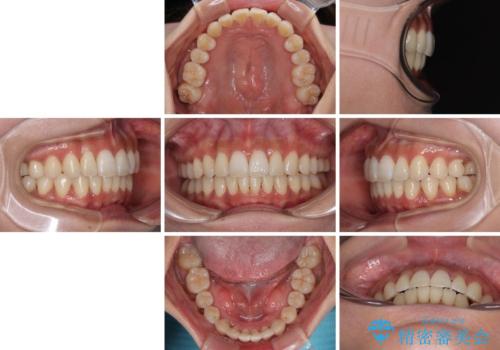

【モニター】上顎前突と奥歯の鋏状咬合 補助装置を用いたインビザライン矯正治療

奥歯の咬み合わせを事前に望ましい位置に改善したことで、インビザライン単独では改善が最も困難な状況を排除することができ、非常に理想的な仕上がりとなりました。